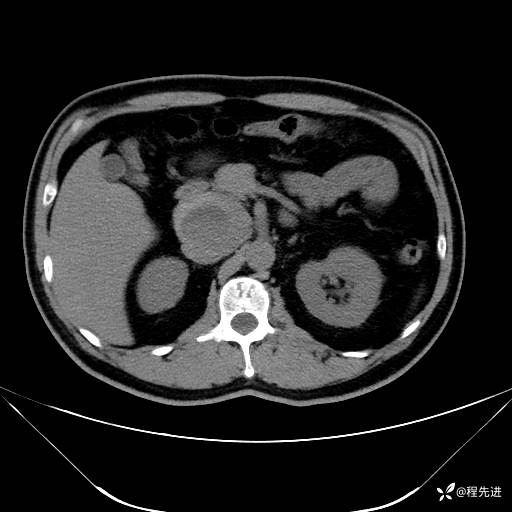

【腹盆】特别精彩病例|发现腹膜后肿物1月余

主诉:发现腹膜后肿物1月余

现病史:患者1月余前查体,行超声检查提示:后腹膜囊实性肿块;慢性胆囊炎伴胆囊内结石;无腹痛腹胀,不伴腹泻发热等;偶感腰背部酸痛。

CT平扫+增强: